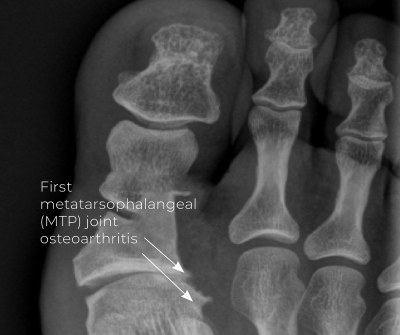

Hallux limitus and hallux rigidus are related degenerative joint conditions that affect the MTP joint of the big toe (Image 3). Hallux limitus is the earlier stage of osteoarthritis characterized by reduced range of motion in the MTP joint, particularly during extension. Common signs and symptoms include mild pain, especially on top of the toe joint, stiffness, the development of a callus under the big toe, and difficulty flexing or extending the toes.

Hallux limitus begins in young adulthood. X-ray evidence shows joint changes in 10 percent of people between 20 and 34 years of age.1 People over 50 have a higher prevalence, with the condition affecting an estimated 1 in 40 adults.2 Without treatment, hallux limitus worsens over time and discomfort increases. Protective spasming in calf muscles might further disrupt the kinetic chain and cause pain and dysfunction.

Hallux rigidus is the advanced stage of joint degeneration, where the joint becomes rigid and immovable. This osteoarthritis of the big toe causes joint space narrowing, cartilage loss, bone spurring, and persistent pain, even at rest. Researchers estimate that hallux rigidus affects about 26.7 percent of people over 50.3